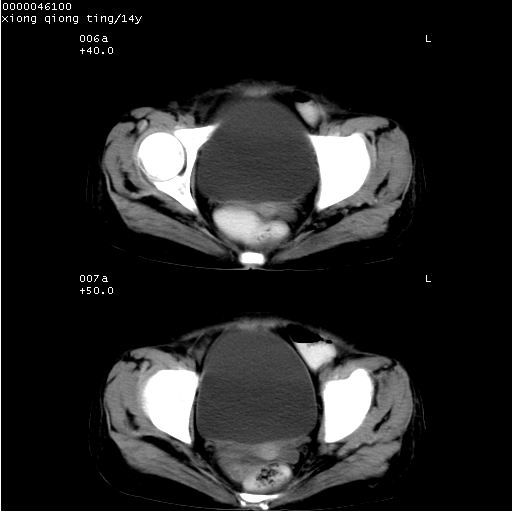

中下腹及盆腔ct轴位平扫+增强扫描(层厚10mm,螺距1.0,重建间隔10mm),图像如下:

(注:患儿检查当日上午9时口服胃肠道对比剂,下午3时许行ct扫描检查,未行对比剂直肠保留灌肠,检查当日患儿腹泻)

中下腹及盆腔ct轴位扫描(ps+ce)提示:腹部肠管明显充气扩张,并见数个不同宽度之气液平面;疑不全性肠梗阻或肠郁张。临床会诊考虑为患儿腹泻,肠郁张所致;后来未经特殊处理,患儿大便恢复正常,亦无腹胀。